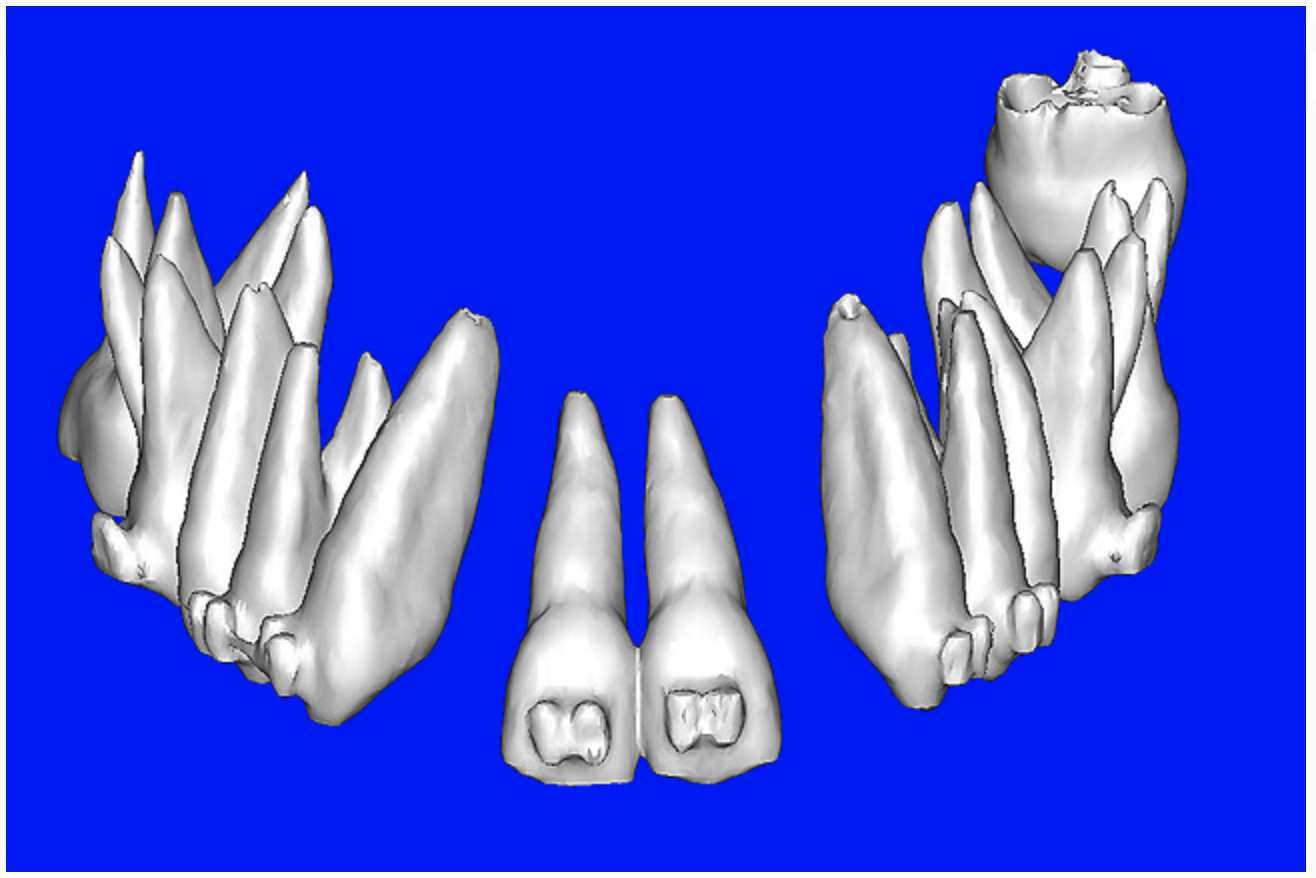

Using different masking (segmentation) and threshold Hounsfield unit values, several new 3D bone volumes can be created which offer invaluable information. To help determine the final position of each implant a new bone model was created with a Hounsfield unit value of 1480, which eliminated all but the densest objects included in the scan data. (Results may vary depending on the CBCT machine used.) The inner and outer layers of bone were removed, leaving the underlying enamel and root structure of the teeth (Figure 8A). After the bone had been stripped away, the root inclinations were examined closely. The most striking findings confirmed the rotated position of the right central, while revealing the slight mesial dilaceration of the root apex, which converged on the space needed for the path of the potential implant (Figure 8B). The schematic shapes of the proposed implants were visualized for the right and left lateral spaces in different rotations of the 3D maxillary arch. It was at this point that a determination was made as to the appropriate implant shape and type that would fit the available space while avoiding encroachment on adjacent tooth roots. A tapered design implant (Tapered Screw-Vent®, Zimmer Dental, www.zimmerdental.com) was chosen from the large virtual library. With the SIMPlant software, the virtual library contains data from dozens of implant manufacturers and realistic computer-aided design representations as seen in Figure 9A through the translucent bone. The position of the left implant can be visualized with adequate mesial-distal distance between adjacent tooth roots (Figure 9B) and a more delicate placement (Figure 9C).

Figure 8a  By using the masking feature, the inner and outer layers of bone were removed virtually, revealing (A) the enamel and root structure of the teeth and the rotated position of the right central and (B) slight mesial dilacerations of the root apex.

Figure 8a

Figure 8b  By using the masking feature, the inner and outer layers of bone were removed virtually, revealing (A) the enamel and root structure of the teeth and the rotated position of the right central and (B) slight mesial dilacerations of the root apex.

Figure 8b